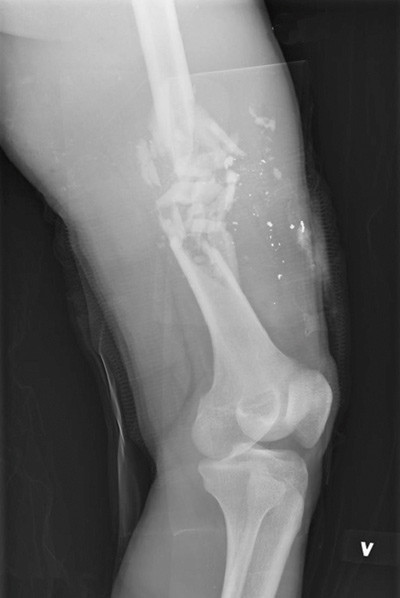

Figure 2:  X-ray of a thigh injury with a fracture and fragments from a high-velocity projectile from a rifle. The…

Figure 2: X-ray of a thigh injury with a fracture and fragments from a high-velocity projectile from a rifle. The projectile is fully mantled and allowed by the rules of war, but it fragments and causes extensive cavitation injuries when hitting a bone. Photo: Norwegian Armed Forces.